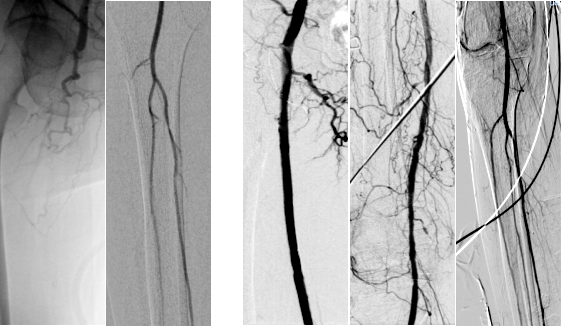

术前CTA图:术前双下肢CT血管成像显示右侧股浅动脉长段闭塞,股浅动脉开口未见显示,右侧胫前动脉上段闭塞。左侧胫前动脉近段重度狭窄、左股动脉中段中度狭窄。

取得患者及家属的同意后,在刘伟波主任医师的指导下,副主任医师王金宝主刀,对患者实施了右下肢动脉血管重建术。按照术前为患者制定的个性化方案,运用腘动脉逆行穿刺及导丝双向会师技术,减少了血管夹层及穿孔、术后再狭窄等情况,最大化地保障了患者的生命安全。术后即时血流恢复,右腿回暖明显。

术前造影 术后造影

手术前后CTA图对比:右图为完成血管重建后,右侧股浅动脉、胫前动脉显影良好,患者右下肢回暖明显。